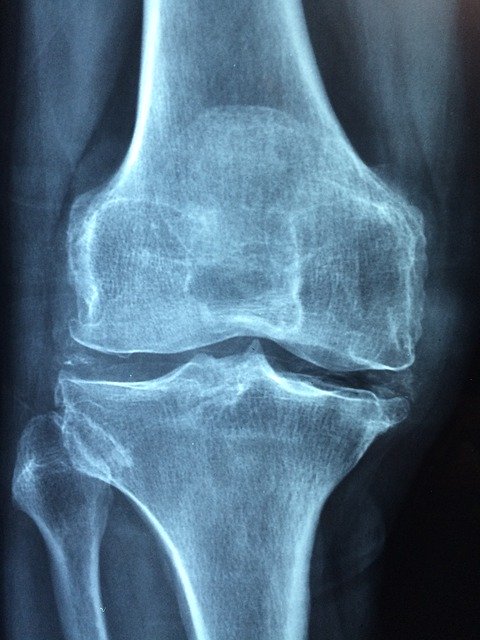

관절염

쇼그렌 증후군은 관절에도 영향을 미칩니다. 쇼그렌 증후군 환자의 50%정도가 관절염을 호소합니다. 주로 류마티스 관절염과 비슷한 증상을 보이며 관절에 통증을 느낄수도 있습니다. 하지만 류마티스 관절염과는 달리 뼈를 깎는 골 침식은 일어나지 않습니다.